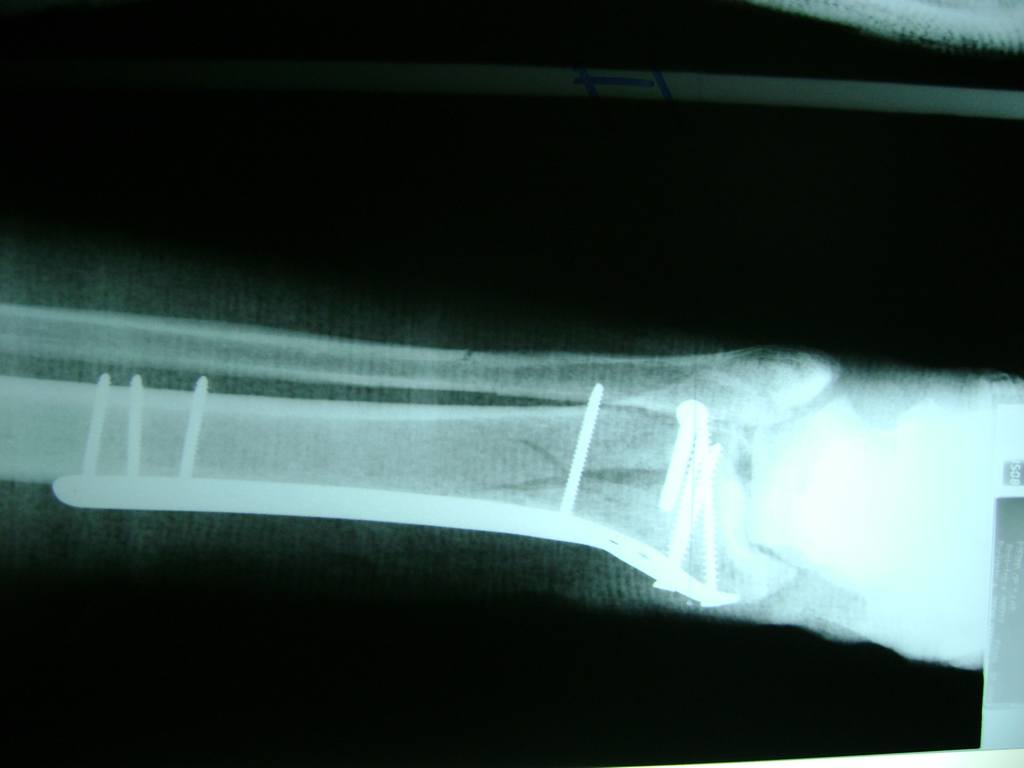

Cuando se necesita cirugía, es probable que esta implique el uso de clavijas de metal, tornillos o placas para sostener los huesos en su lugar mientras la fractura se consolida. Los elementos de soporte pueden ser temporales o permanentes.